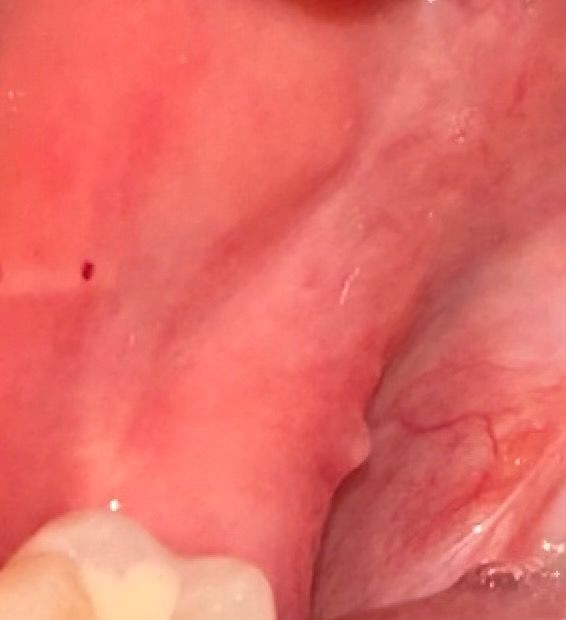

입 안 뾰루지?인지 뭐가 생겼는데 뭔가요?

어금니 쪽 입 안 볼에 뽀루지가 자꾸 생겼다 없어지는데 이게 뭔가요? 옆에 빨간 점도 있는데 괜찮은가요? 치과에 가야할까요?

단순 상처인 것으로 보입니다. 뜨거운 음식물 자극이나 딱딱한 음식에 찔려 생겼을 가능성이 높습니다. 그냥두면 저절로 없어집니다.

사진에 보이는건 볼살이 씹혀서 생긴거 같습니다. 큰 문제가 잇는건 안니 너무 걱정하지 않으셔도 됩니다.

볼살을 씹으면서 생긴 것으로 보입니다. 치과 가실 필요는 없으시고 자극만 조심하시면 됩니다.

사진만 봐서는 정확한 진단은 어렵습니다 계속 반복적으로 생긴다면 구강내과를 가보시기 바랍니다